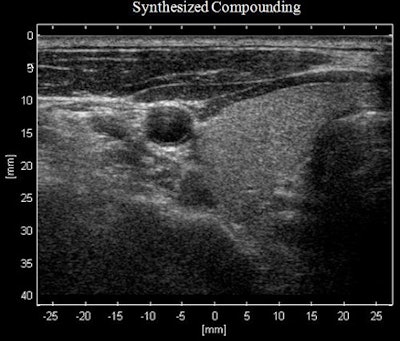

In a comparison with standard imaging techniques, the so-called synthetic steered continuous transmit/receive focusing (SSCTRF) images had better image quality and higher contrast-to-noise ratios and improved diagnostic confidence.

To compare traditional images with the enhanced SSCTRF images, the researchers collected contrast ultrasound loops from a Zonare ZS3 ultrasound system (Mindray) using two different transducers. The loops were processed with traditional methods, extracting single cubic-fundamental and single B-mode images.

The image data were also processed to extract up to six cubic-fundamental images and three harmonic images along with three B-mode images. The six cubic-fundamental images consisted of two images created by weighting and adding combinations of the pulse sequence, and four images that were then constructed through SSCTRF techniques to generate two steered-left and two steered-right images. The same technique was used to generate three standard harmonic and three B-mode images. The traditional images were compared with the SSCTRF images.

Image loops generated using SSCTRF techniques showed improved contrast resolution, better signal-to-noise ratios, and sharper border delineation, and preserved tissue perfusion kinetics without destroying additional microbubbles, providing enhanced visualization and higher diagnostic confidence, McLaughlin said.